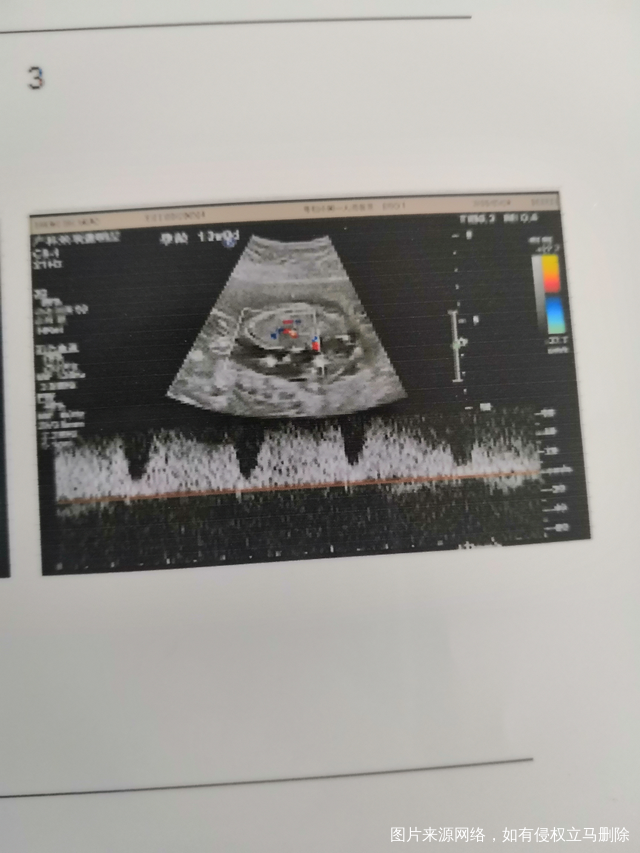

有没有经验帮忙看看性别,

第一个是儿子,这胎想要女儿[冒心心]忘有经验的分享下经验,给点勇气,谢谢😜